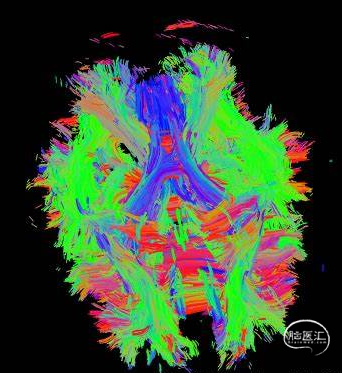

DTI(是研究脑内脑白质纤维束的成像方法,反映不同脑部区域的纤维和网络节点间的纤维密度)研究也证实:脑白质路径易受癫痫反复发作的影响。这种改变和癫痫发病的时长相关,癫痫病理灶所在的一侧大脑区域间的连接与对侧相应正常区域连接有不同。

图四,弥散张量成像(DTI)可以无创地观察脑白质微观结构